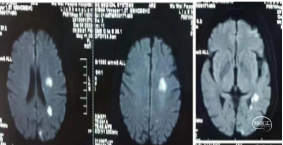

重症脑血管病管理:经甘露醇、白蛋白、3%氯化钠脱水、高压氧、依达拉奉、吡拉西坦脑保护治疗13天水肿消退,脑中线无移位,左侧大脑中动脉区域较前变淡。脑沟脑回显示清楚。

患者意识清楚,部分感觉性失语(部分听不懂),能说话,左侧肢体功能正常,配合指令活动。右侧上肢肌力0级,下肢肌力Ⅱ级+。